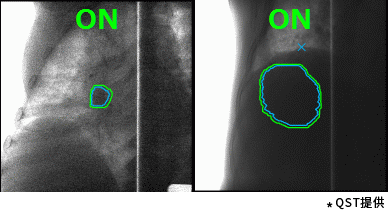

德赢vwin8868官网的重离子癌症放射治疗系统具有高速3D扫描,患者自动定位,小型化重离子旋转机架(搭载德赢vwin8868官网自研超导磁铁实现重量和体积的大幅缩小)等差异化技术。实时成像的呼吸门控是照射技术与重复扫描技术的结合,能够对伴随呼吸运动的肿瘤进行快速、准确的照射,且保证剂量分布均一性。特别是,德赢vwin8868官网凭借自身先进的超导技术的加持,使旋转机架得以逐渐小型化。这一成果直接推动了重离子旋转机架的商业化普及。应用旋转机架治疗,可从360度任意角度进行照射,避开正常组织和危及器官。治疗过程中一次定位,避免了移动患者造成的内部脏器位移,实现精准治疗,同时提高治疗效率,增加治疗人数,在同类型产品中独具技术优势。

高速扫描+呼吸门控照射(动图) |